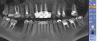

serikovigor Опубликовано 27 июля, 2013 Поделиться Опубликовано 27 июля, 2013 Здравствуйте, уважаемые стоматологи!Имеется 7-ка с гранулемой\кистой. Удалять не хочется - т.к. соседних нет, хочется сделать мост.Посоветуйте, что делать. Ходил к хирургу - говорит попробуйте перелечить,обошел нескольких терапевтов - все отказываются...Искать терапевта, который согласится, или все же удаление? Ссылка на комментарий